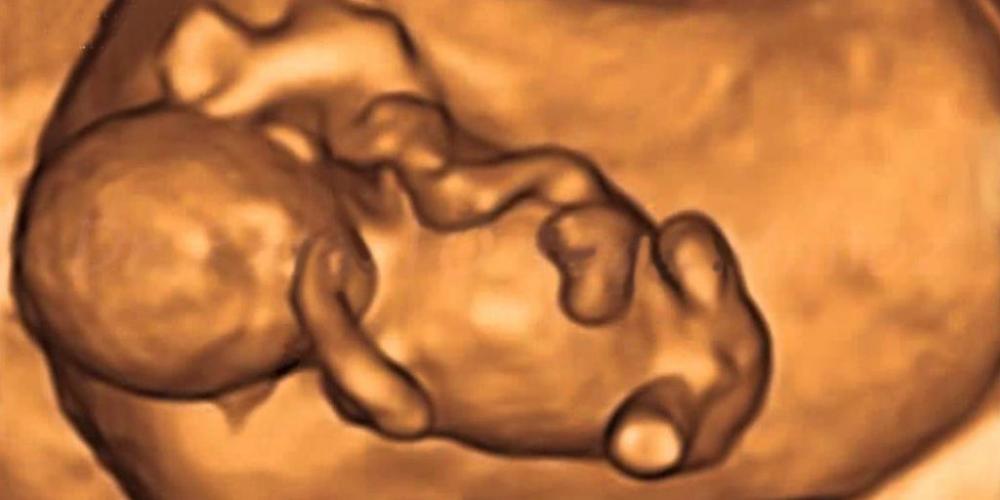

¡JUGATE POR LA VIDA!